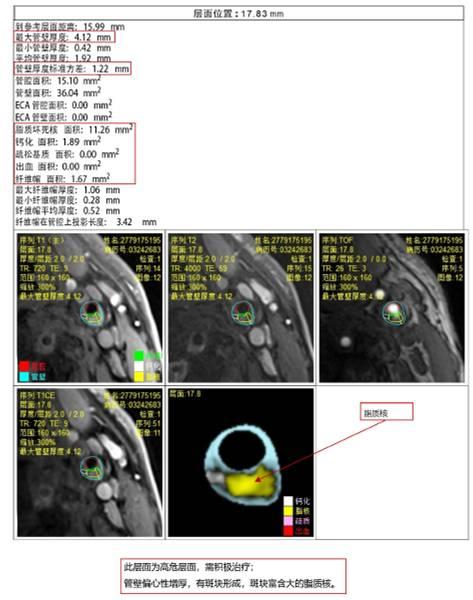

实例说明:

(a)